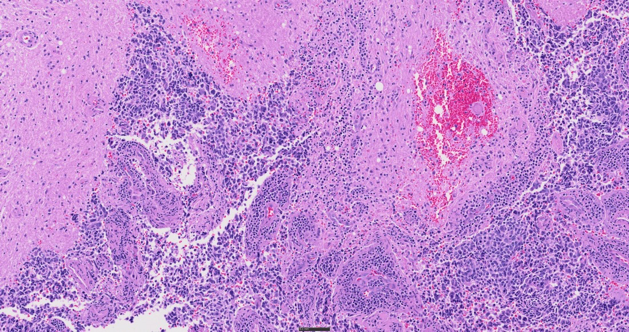

The SLIDEVIEW VS200 system offers high-resolution slide scanning for advanced research applications, such as neuroscience, cancer and stem cell research, and spatial biology. With the flexibility of up to 10 imaging modes, multiplexing capabilities, and multiple magnifications up to 100X, the system delivers outstanding image quality for quantitative analysis.

SLIDEVIEW VS200 for Digital Pathology

As a flexible yet intuitive scanner, the SLIDEVIEW VS200 system enables your team to digitize a wide range of sample types with minimal training. The VS200 system helps you achieve a fully digital workflow for pathology with versatile slide scanning, outstanding image quality, and flexible integration options. Get the evidence you trust for standard and specialty samples to make breakthrough decisions with confidence.